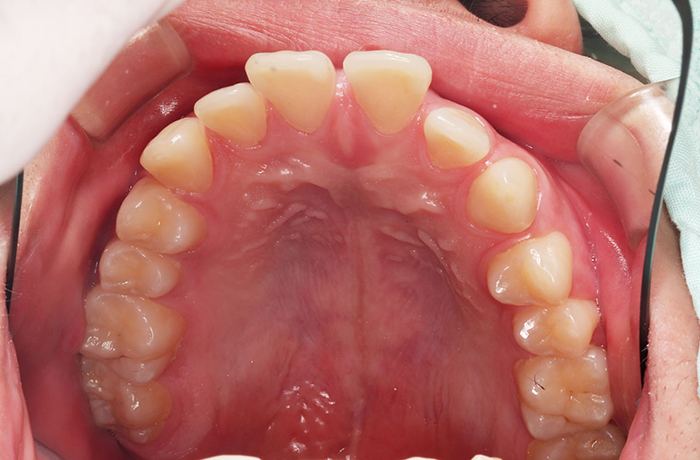

A様

治療前

before

年齢 31歳

性別 女性

治療名称 マウスピース型カスタムメイド矯正歯科装置(インビザライン)・コンプリヘンシブパッケージ(難症例)

総額治療費用 935,000円(税込10%) 金額備考 精密検査料・診断料 33,000円(税込10%)

治療期間 3年4か月 通院頻度など 1か月ごと(途中から3~4か月ごと)

患者の症状 叢生、正中のずれ、上顎左右側切歯の口蓋側転位(交叉咬合)

治療方法 非抜歯で、マウスピース型カスタムメイド矯正歯科装置(インビザライン)による矯正

歯列弓を拡大することで非抜歯を可能にしました。

治療結果 側切歯の交叉咬合は解消、上下正中のずれも改善し咬み合わせが良くなりました。